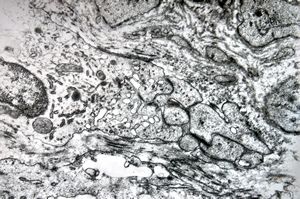

F,25y. | giant multinuclear osteoclast - aneurysmatic cyst - tibia